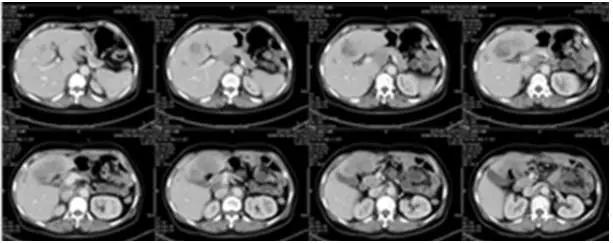

三线阿帕替尼+CPT11

2016年1月至2月,患者开始接受阿帕替尼425mg+伊立替康0.24g d1q3w的三线治疗共2个疗程。2016年3月1日疗效评估为SD,肝左叶及尾状叶低密度影,较前增大17%。从2016年3月起,将剂量调整为阿帕替尼加量至850mg +伊立替康0.24g d1 q3w,又接受了2个疗程的治疗。

图6 2016年3月1日CT